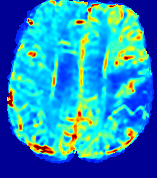

LesionRefer to captionRefer to captionRefer to captionRefer to captionRefer to captionRefer to caption𝐕rgbsubscript𝐕𝑟𝑔𝑏{\bf{V}}_{rgb}Refer to captionRefer to captionRefer to captionRefer to captionRefer to captionRefer to caption𝐕2subscriptnorm𝐕2{\|\bf{V}}\|_{2}Refer to captionRefer to captionRefer to captionRefer to captionRefer to captionRefer to captionRefer to caption3.53.53.52.82.82.82.12.12.11.41.41.40.70.70.70.00.00.0(mm/s)𝑚𝑚𝑠(mm/s)D𝐷DRefer to captionRefer to captionRefer to captionRefer to captionRefer to captionRefer to captionRefer to caption0.0200.0200.0200.0160.0160.0160.0120.0120.0120.0080.0080.0080.0040.0040.0040.0000.0000.000(mm2/s)𝑚superscript𝑚2𝑠(mm^{2}/s)Slice #1Slice #2Slice #3Slice #4Slice #5Slice #6

Figure 3: PIANO feature maps for one stroke patient, where the lesion is located in the left hemisphere. Top row: segmented stroke lesion region (white) on different slices, obtained from ISLES 2017. The corresponding slices for the PIANO feature maps are shown in the following rows.

For a better insight into an estimated velocity field 𝐕𝐕{\bf{V}} and diffusion field 𝐃𝐃{\bf{D}}, we compute the following maps: (1) 𝐕rgbsubscript𝐕𝑟𝑔𝑏{\bf{V}}_{rgb}: Color-coded orientation map of 𝐕=(Vx,Vy,Vz)T𝐕superscriptsuperscript𝑉𝑥superscript𝑉𝑦superscript𝑉𝑧𝑇{\bf{V}}=(V^{x},V^{y},V^{z})^{T}, obtained by normalizing 𝐕𝐕{\bf{V}} to unit length and mapping its 3 components to red, green, blue respectively; (2) 𝐕2subscriptnorm𝐕2\|{\bf{V}}\|_{2}: 222 norm of 𝐕𝐕{\bf{V}}; (3) D𝐷D: scalar field in Eq. 5.

Fig. 3 and Fig. 4 show the PIANO feature maps estimated from two ISLES 2017 patients: all are highly consistent with the lesion in both cases. Details of the blood flow trajectories are revealed in 𝐕rgbsubscript𝐕𝑟𝑔𝑏{\bf{V}}_{rgb} by the ridged patterns and the sharp changes of colors in the unaffected (right) hemisphere, while the flat patterns appearing within the lesion provide little directional information about the velocity and indicate low velocity magnitudes. Velocity magnitudes are more directly visualized via 𝐕2subscriptnorm𝐕2\|{\bf{V}}\|_{2}, from which one can easily locate the lesion where 𝐕2subscriptnorm𝐕2\|{\bf{V}}\|_{2} is low. D𝐷D also indicates lower diffusion values in the lesion, though with less contrast potentially due to the fact that it captures the accumulated effect of CA diffusion at the voxel-level.